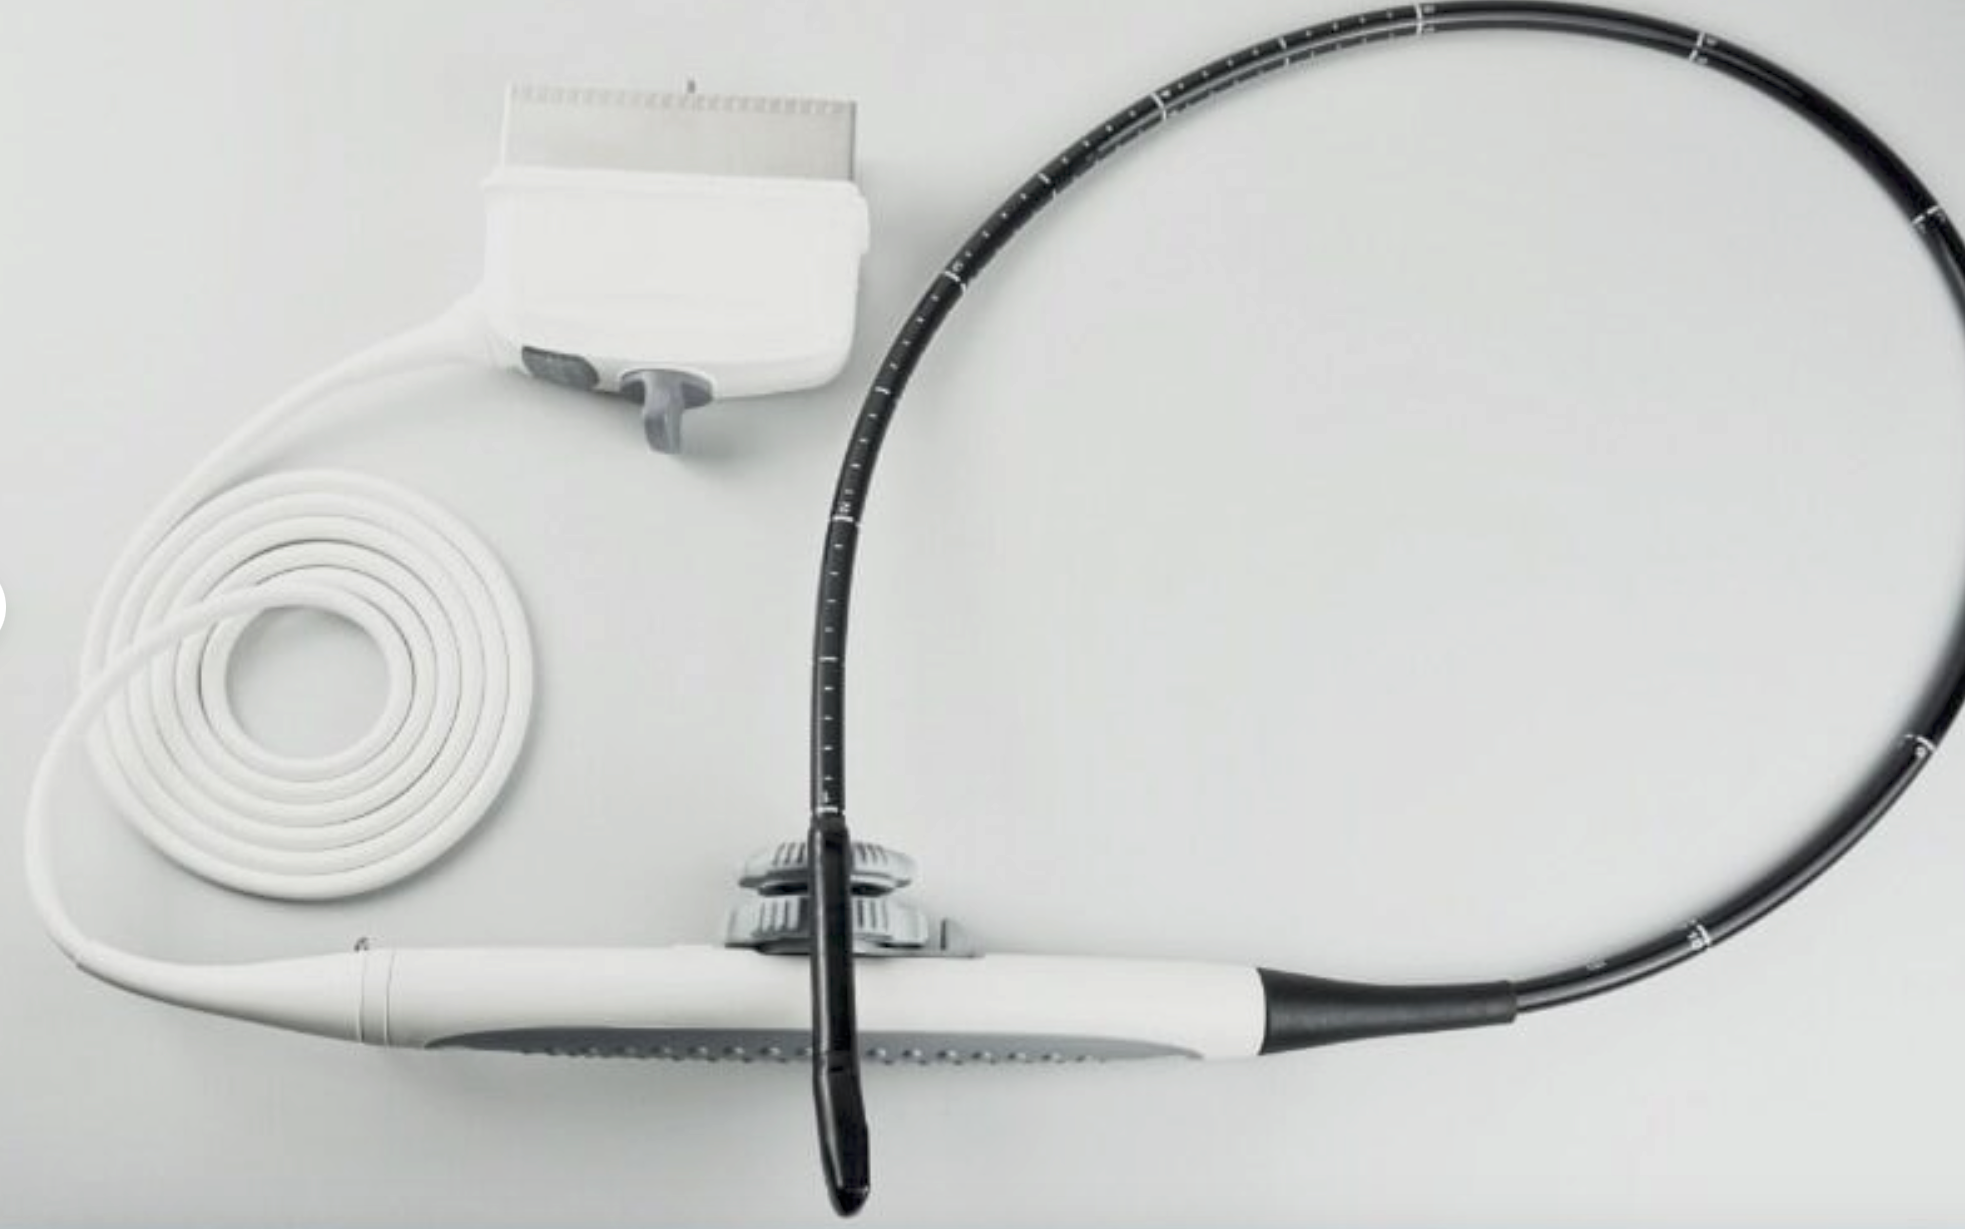

Main Unit: KeeboTouch 20V |

Micro-convex Probe |

Linear Abdominal |

Rectal Linear Probe |

Convex Probe |